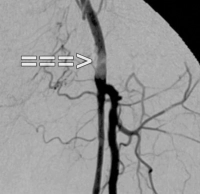

Filmbeispiel: TASC C → offene Rekonstruktion

AVK Stadium IIb links (Gehstrecke unter 100 m). Die präoperative DSA zeigt:

- eine subtotale Stenose der Arteria femoralis communis

- einen langstreckigen Verschluss der Arteria femoralis superficialis im Adduktorenkanal

- Teilverschlüsse der Unterschenkelarterien